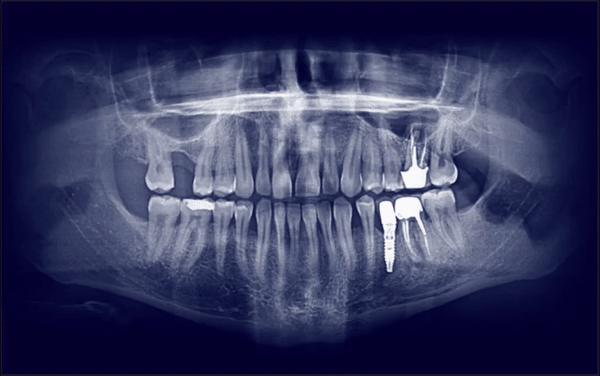

At Allisone, we use Deep Learning, a branch of artificial intelligence, to create the most reliable, robust and accurate state-of-the-art software. Deep learning is a type of learning based on artificial neural networks organized into successive layers of processing used to extract high-level features from data. By showing annotated X-ray images to Allisone, our Artificial Intelligence system is able to learn to analyze them instantly and reproduce its pattern of reading the features to give practitioners a second read of the dental xray.